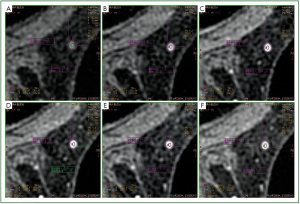

In 115 patients that were examined, 376 abnormalities were investigated. For each one of them, an enhancement kinetic curve was derived (from the images of the multi-phasic sequence - Vibrant) both using the calculation software of the system and manually. In 81 (21.5%) cases, a change of the enhancement kinetic curve type was found between the two methods (Figure 3,5).

Figure 5. In this case the ROI was positioned in two different regions [image (A), image (C)] in the third phase of the dynamic sequence. (B) Kinetic curve of type I, which correspond to the ROI of image (A). (D) Kinetic curve of type II, which correspond to the ROI of image (C). Image e and f show derivation of the kinetic curves corresponding to images (A) and (C) using the manual kinetic curve derivation procedure, which were found to be of type II.